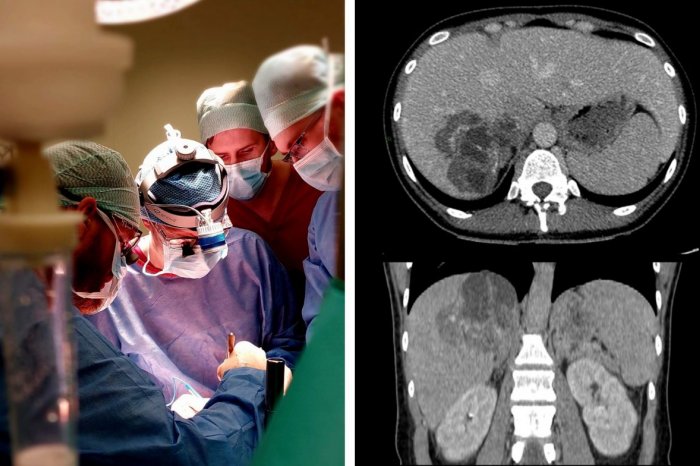

Vo Fakultnej nemocnici s poliklinikou F.D. Roosevelta v Banskej Bystrici vzniklo v apríli Centrum echinokokózy, špecializované pracovisko, ktoré bude komplexne riešiť problematiku tohto závažného parazitárneho ochorenia. Informovala o tom hovorkyňa nemocnice Ružena Maťašeje so slovami, že centrum vzniklo ako reakcia na neustále stúpajúcu incidenciu echinokokózy spôsobenej pásomnicou líščou na Slovensku.

Rooseveltova nemocnica sa podľa Maťašeje za posledné roky stala prirodzeným centrom pre pacientov s echinokokózou vďaka niekoľkým kľúčovým faktorom. „Vo FNsP F.D. Roosevelta pokrývame všetky potrebné diagnostické a terapeutické procesy pod jednou strechou. Od serologických a zobrazovacích vyšetrení, intervenčných zákrokov až po resekčnú a transplantačnú chirurgiu. A v tom je naša nemocnica na Slovensku unikátna,“ uvádza MUDr. Július Janek, PhD., prednosta Kliniky transplantačnej chirurgie SZU.

„Echinokokóza, najmä jej alveolárna forma, sa správa ako nádorový proces s inváziou do štruktúr pečene a okolitých orgánov,“ upozornila Maťašeje so slovami, že mortalita u neliečených alebo nedostatočne liečených pacientov dosahuje až 90% v priebehu 10–15 rokov od stanovenia diagnózy.

„Pribúdajú pokročilé štádia alveolárnej echinokokózy u veľmi mladých ľudí, čo nás núti prinášať nové chirurgické postupy, ktorými by sme im vedeli pomocť. Rozhodnúť o ideálnom terapeutickom manažmente pacienta s tak rozsiahlim postihnutím je možné len vtedy, ak máte k dispozícii všetky dostupné modality liečby. Za obdobie posledných rokov sme vyšetrili takmer 250 pacientov s podozrením na toto ochorenie. U 130 pacietov bolo ochorenie aj potvrdené,“ vysvetľuje MUDr. Martin Sirotňák, vedúci lekár Centra.

Liečba závisí od typu parazita, pričom každý pacient s potvrdenou diagnózou by mal podľa Maťašeje kontinuálne a dlhodobo užívať antiparazitickú liečbu. „Pri cystickej echinokokóze sa manažment liečby stanovuje podľa vzhľadu, veľkosti a lokality cýst – od perkutánnych intervenčných zákrokov cez chirurgické odstránenie až po transplantáciu pečene. Pri alveolárnej echinokokóze je cieľom úplné odstránenie parazitickej lézie, čo sa dosiahne "kuratívnou“ operáciou kombinovanou s 2-ročnou liečbou antiparazitikami," dodala hovorkyňa so slovami, že základom prevencie je dôkladná hygiena rúk, umývanie ovocia a zeleniny pred konzumáciou, vyhýbanie sa kontaktu s výkalmi zvierat a zabezpečenie pravidelného odčervovania domácich miláčikov.